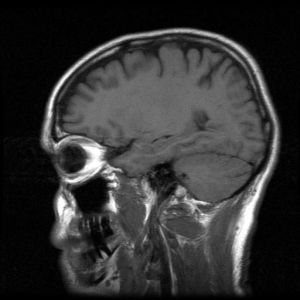

Understanding Traumatic Brain Injuries (TBI): Types, Symptoms, and Challenges

A traumatic brain injury (TBI) is a complex injury with a broad spectrum of symptoms and disabilities. The impact on a person’s life depends heavily on the type, location, and severity of the damage. For injury victims and their families in Illinois, understanding the nature of the injury is the first step toward appreciating the long road to recovery and the importance of securing adequate legal and medical support.